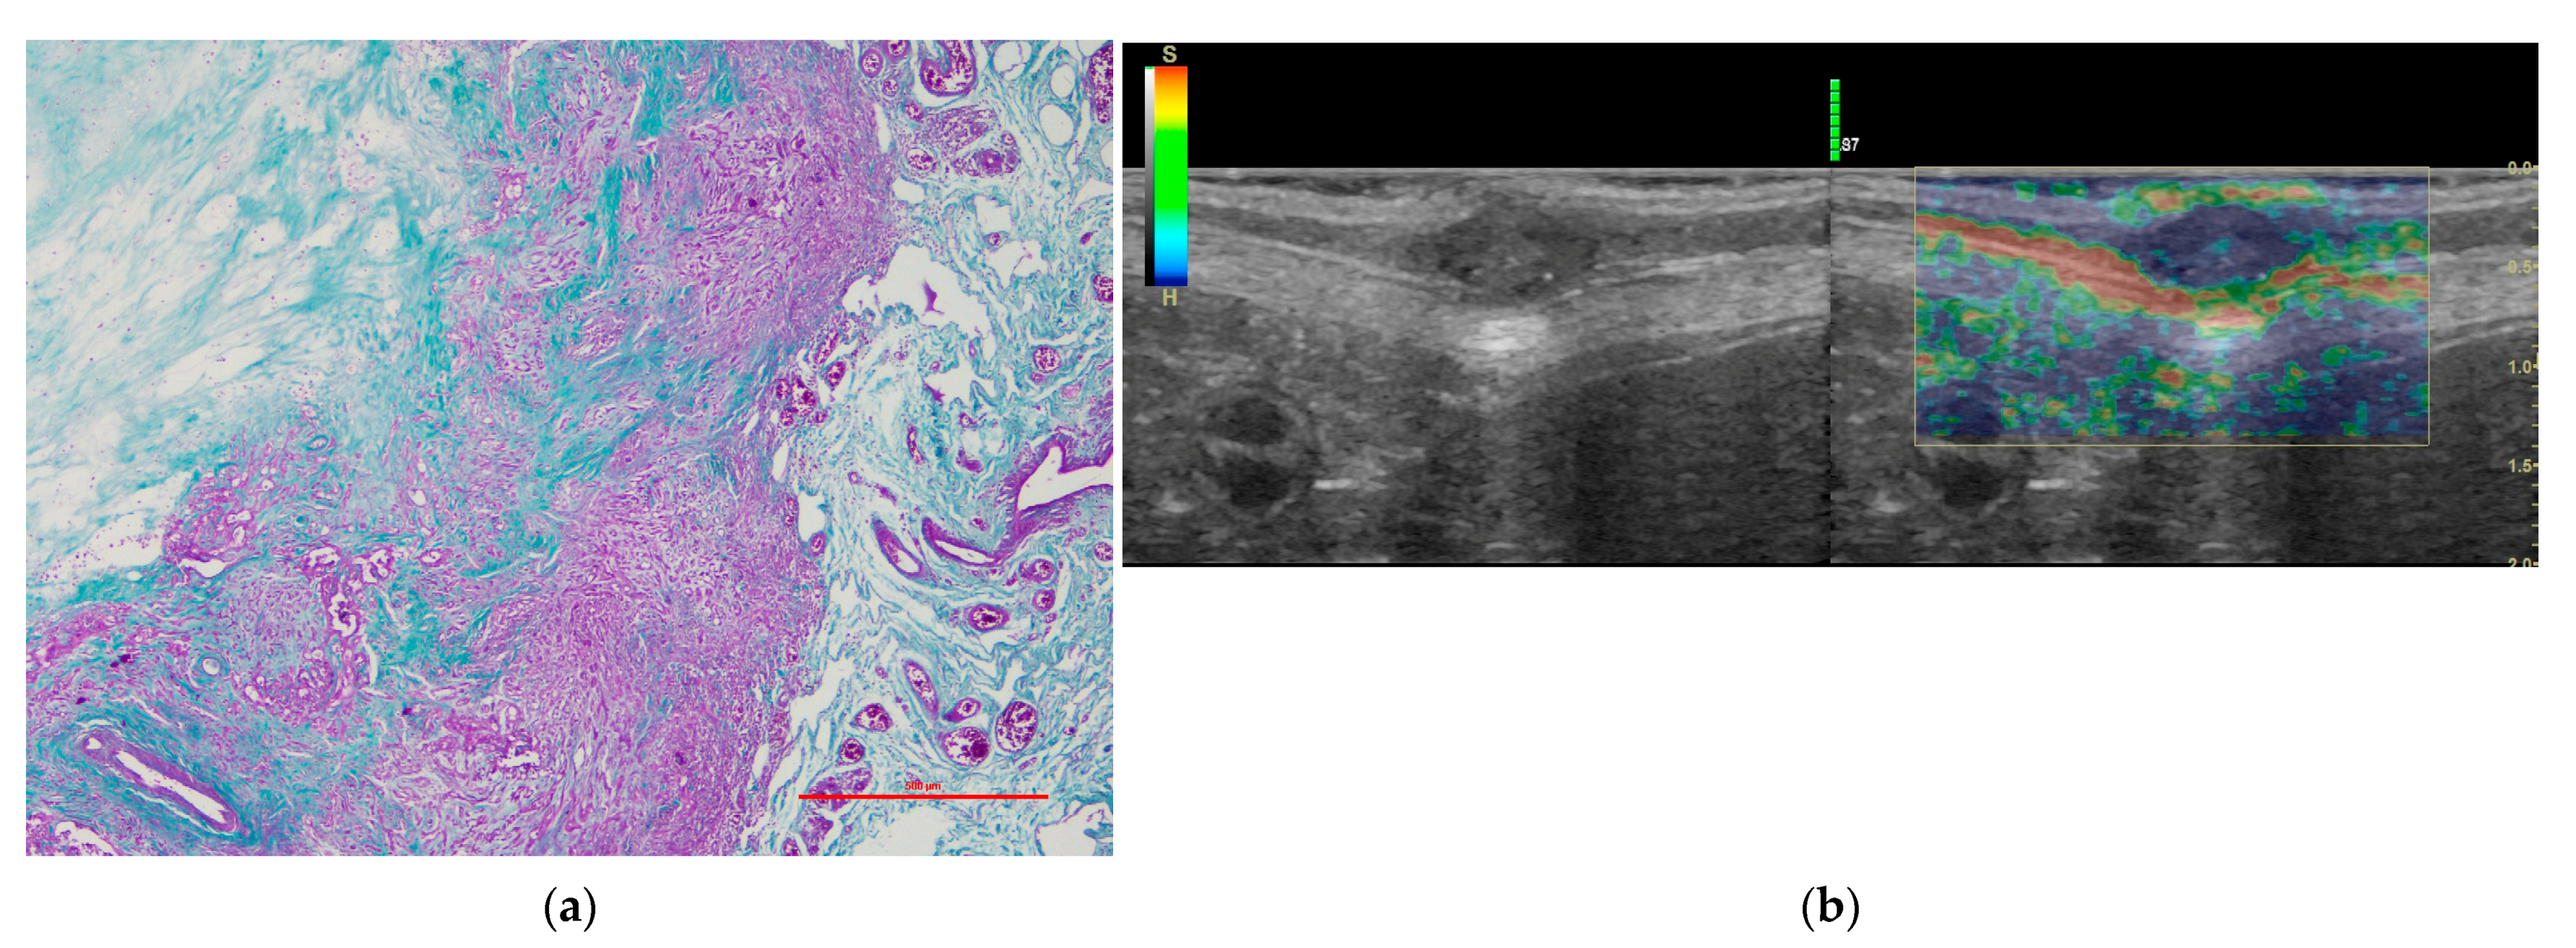

3.2. Histological Study

3.3. Elastography Ultrasound